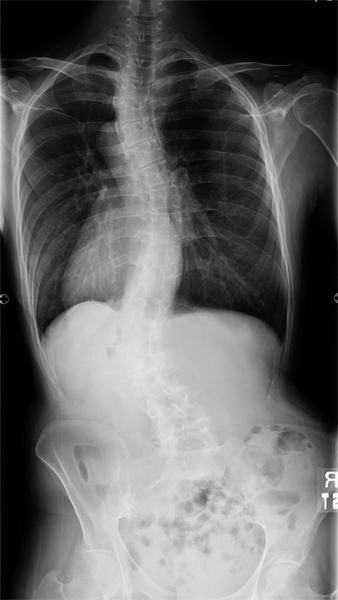

思春期特発性側弯症、立位全脊柱X線正面像

13歳女性、T6-L1でCobb角58°の側弯を認める。